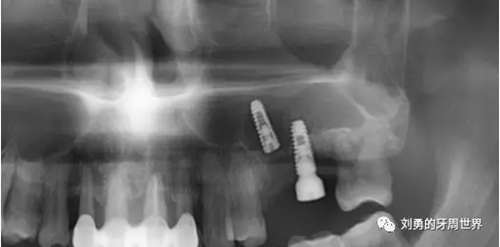

在手術(shù)之前行ct檢查如下圖:

可見B5種植體已經(jīng)脫落進(jìn)入上頜竇,而上頜竇黏膜已經(jīng)出現(xiàn)明顯的炎癥,上頜竇黏膜明顯增厚,(在二期切開手術(shù)之前上頜竇黏膜厚度正常)。而在ct上可以看到左側(cè)上頜竇中鼻道開口不通暢。